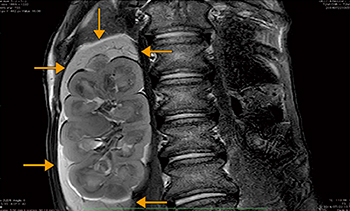

MRI検査の対象動物は9割以上がイヌであり,検査件数は週に3〜5件。約8割が臨床目的で,中枢神経系の検査が中心となる。臨床症状から,ダックスフンドなどに多い椎間板ヘルニアや,高齢化により増えている脳腫瘍,特発性脳炎などが疑われる場合にMRIが選択される。また,MRIにより,従来はイヌやネコには少ないとされていた脳梗塞や脳出血も次々に見つかっている。

検査では,イヌやネコには膝用コイルを用い,大型動物は寝台埋め込み型の脊椎用コイルや腹部用コイルを組み合わせて撮像している。T2強調画像,T1強調画像,FLAIR,造影T1強調画像を基本に,拡散強調画像やT2*強調画像,脂肪抑制を必要に応じて追加している。三浦准教授は,特に3D撮像の有用性を強調する。

「例えば数cmしかない脳に対して,6mm厚のスライス撮像では病変を見落とす可能性があり,微小な下垂体などをとらえることも困難でした。TRILLIUM OVALでは3D撮像後に0.6mmでの再構成も可能ですし,3Dでスクリーニングをすれば,スライス位置を適切に設定できます。紹介元に返す時にも,“見えなかった”と“見たけれど何もなかった”ではまったく違います」